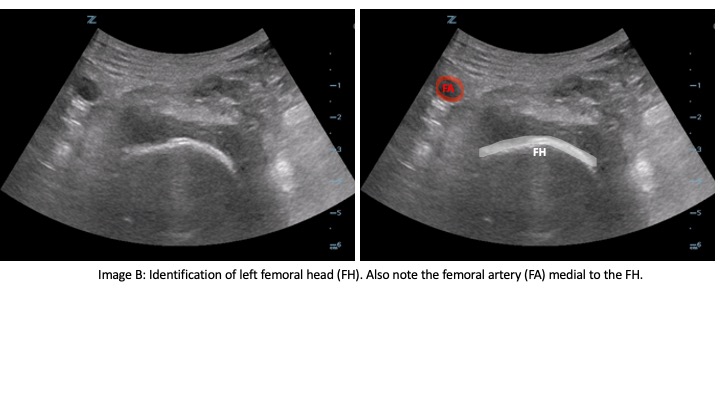

The curvilinear probe is used at an oblique angle parallel to the IL with probe marker to the patient's right side. The linear probe may be used in patients who are thin for better image resolution. Initially, the probe should be positioned inferior to the IL to identify the femoral head (Image B). Then the probe can be moved cranially until the anterior inferior iliac spine (AIIS) and iliopubic eminence (IPE) of the ilium are visualized (Image C). The femoral artery, femoral nerve, iliacus muscle and psoas tendon should be identified. The femoral nerve generally lies right above the psoas tendon on top of the iliacus muscle and is just lateral to the femoral artery. The target is the subfascial plane located underneath the psoas tendon and above the ilium. A 20G or larger long spinal needle or echogenic nerve block needle is inserted in a lateral-to-medial approach until contact with the ilium is made underneath the psoas tendon (Image D). Hydrodissection of the fascial plane using saline initially helps to visualize the correct location before injecting 20 CCs of long-acting anesthetic, such as ropivacaine or bupivacaine with epinephrine. The block has been shown to be effective with a lower concentration of local anesthetic such as 0.25% bupivacaine with epinephrine.